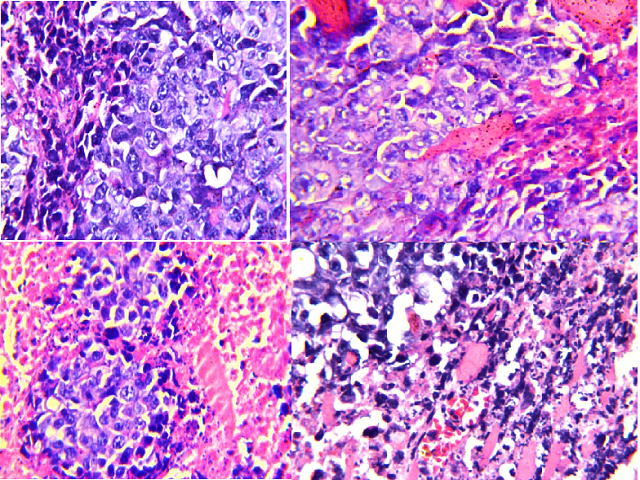

ArticleViewAbstractPharmacognosy Journal,2019,11,5,849-857.DOI:10.5530/pj.2019.11.137Published:September 2019Type:Original ArticlePhenolic Profile and In Vivo Cytotoxic Activity of Rice Straw ExtractMeselhy KM, Shams MM, Sherif NH, and El-Sonbaty SM Meselhy KM1,*, Shams MM2, Sherif NH3,4, El-Sonbaty SM5 1Department of Pharmacognosy, Faculty of Pharmacy, Cairo University, EGYPT. 2Department of Medicinal Plants and Natural Products, National Organization for Drug Control & Research (NODCAR), Giza, EGYPT. 3Drug Radiation Research Department, National Centre for Radiation Research and Technology (NCRRT), Atomic Energy Authority, Nasr City, EGYPT. 4Pharmacognosy Department, Faculty of Pharmacy, Nahda University, Beni Suef, EGYPT. 5Department of Radiation Microbiology, The National Center for Radiation Research and Technology (NCRRT), Atomic Energy Authority, Nasr City, EGYPT. Abstract:Background: Previous work of our team exhibited that rice straw (RS) has antitumor activity in vitro and inhibit proliferation of liver, lung, prostate, and breast cancer human cell lines. In this work, we extended our research to screen the antitumor activity of RS ethanol extract as a single treatment and in the presence of combined radiotherapy with a low dose of gamma radiation against murine Ehrlich solid carcinoma (EAC) model. Objective: To evaluate the most common waste in Egypt RS to screen out its in vivo cytotoxic activity and as combined therapy with radiotherapy. Method: Tested sample RS was investigated for its content of phenolics by LC/MS/MS, in addition, ethanolic extracts of the tested sample were investigated as antitumor on female mice inoculated with EAC cells as a single treatment and in the presence of combined radiotherapy with a low dose of gamma radiation (LDR). Results: LC/MS/MS revealed that rice straw was rich in phenolic acids (vanillic, p-coumaric, ferulic, and sinapic acid) along with catechin and flavonoids aglycones (quercetin, apigenin, and kaempferol). Rice straw and/or exposure to a low dose of γ-radiation caused a marked suppression of tumor growth and induced significant reduction in VEGF level & in IL-6 level with significant elevation in IL-10 serum level. Rice straw caused a significant down regulation in the gene transcription level of MCL1 and b-catenin, and a significant up-regulation of Caspase-3 and Bax gene expression. RS extract and LDR (EC + RS + R group) revealed that there was a mild form of necrosis with severe apoptosis in the tumor cells. Conclusion: From the aforementioned results, it can be concluded that RS/LDR effectively and synergistically work towards inhibition of cancer cell proliferation. These findings were well supported with histopathological studies suggesting that RS/low dose gamma radiation can serve as a good therapeutic agent against cancer but still need further clinical studies. Keywords:Cytotoxic, Histopathology, LC/MS/MS, Phenolics, Rice strawView:PDF (5.36 MB) PDF Images Photomicrographs of sections in solid Ehrlich carcinoma (EC) stained by H and E. (A): Section in muscular tissue of EC bearing mice; (B): Section in muscular tissue of EC treated with RS extract; (C): Section in muscular tissue of EC treated with gamma irradiation; (D): Section in muscular tissue of EC treated with RS extract and gamma irradiation, H and E, ×80. ‹ Pharmacogn J, Vol 11, Issue 5, Sep-Oct, 2019 up Protective Effect of the Ethanolic Extracts of Leaves of Chuquiraga spinosa Less and Baccharis genistelloides on Benign Prostatic Hyperplasia in Rats ›